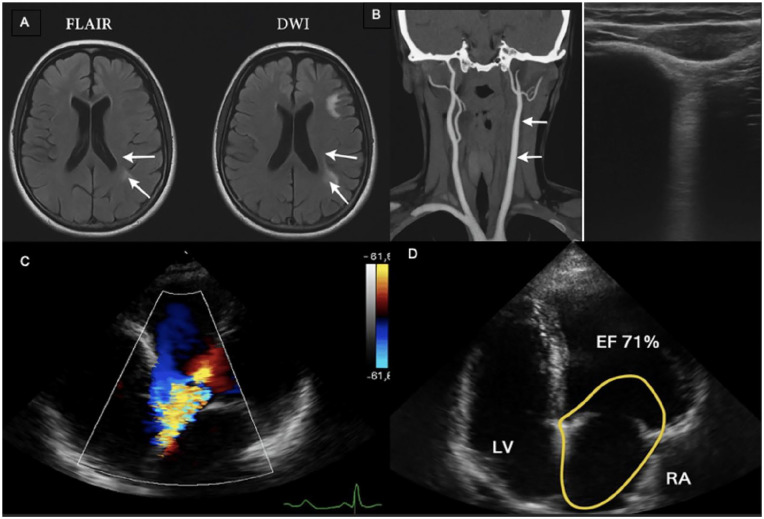

Alien Hand Syndrome (AHS) is a rare neurological condition characterized by involuntary, goal-directed movements of a limb without conscious control. It is most often associated with stroke in specific brain regions, including the medial frontal and parietal cortices. We report the case of a 33-year-old male with no previous medical history who presented with involuntary movements of the left upper limb, describing it as "moving on its own." Neurological examination was unremarkable, but MRI revealed multiple cortical infarcts in the right frontal and parietal lobes, with both acute and subacute features. Extensive workup ruled out vascular stenosis, dissection, and hypercoagulable states. Transthoracic echocardiography showed normal left ventricular function and a hypermobile interatrial septum. Transesophageal echocardiography confirmed the presence of a tunnel-shaped patent foramen ovale (PFO; 0.4 mm × 0.3 mm) without thrombus. No deep vein thrombosis or other embolic sources were found. A diagnosis of cardioembolic stroke due to paradoxical embolism through a PFO was established. The patient underwent successful percutaneous closure and started dual antiplatelet therapy. At follow-up, AHS symptoms improved significantly. This case highlights an atypical initial presentation of ischemic stroke in a young adult and emphasizes the need for early neuroimaging and comprehensive cardiac evaluation in cryptogenic strokes.